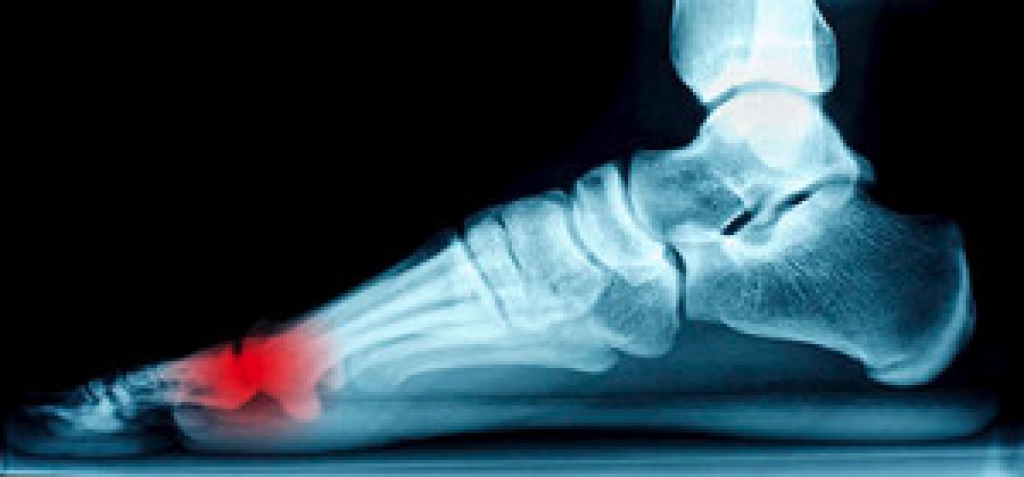

The tendons attached to the bones located on the sole of the foot are referred to as the sesamoid bones. If these tendons become inflamed, typically resulting from an injury, a condition known as sesamoiditis occurs. A common symptom is pain experienced under the ball of the foot while walking, or discomfort may be felt from standing on your toes because the tendons are stretched. Choosing to wear high heels in addition to participating in sports that involve running and jumping may be common causes of this condition. Treatment may include ceasing the activity that caused sesamoiditis and considering a consultation with a podiatrist for custom-made insoles to provide relief.

Sesamoiditis is a condition of the foot that affects the ball of the foot. It is more common in younger people than it is in older people. It can also occur with people who have begun a new exercise program, since their bodies are adjusting to the new physical regimen. Pain may also be caused by the inflammation of tendons surrounding the bones. It is important to seek treatment in its early stages because if you ignore the pain, this condition can lead to more serious problems such as severe irritation and bone fractures.